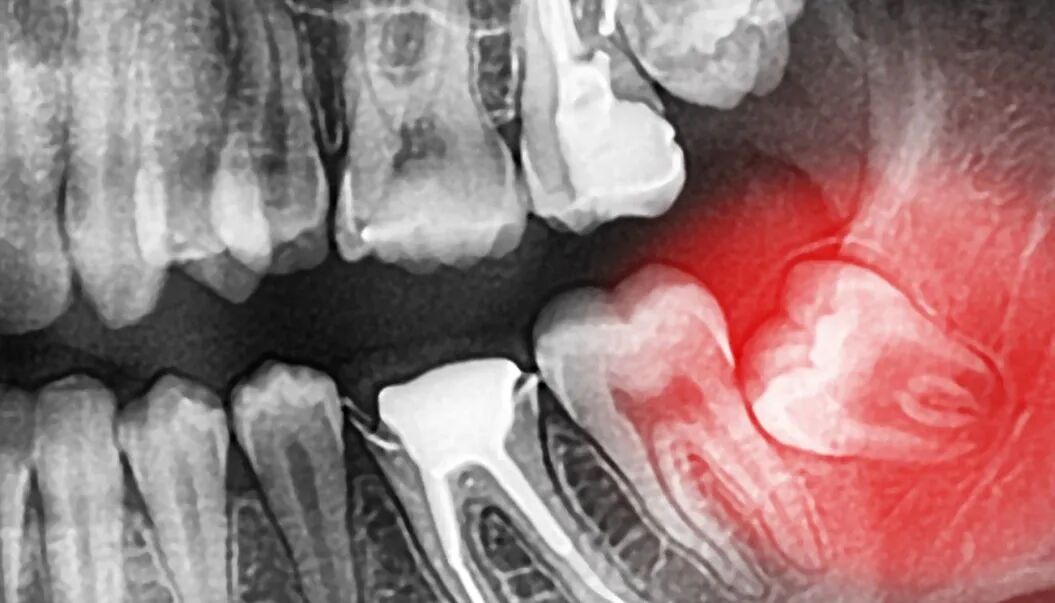

虽然拔阻生牙很贵,特别是没有感觉到疼的人可能会拒绝拔阻生牙,然后暗自窃喜,省了一笔钱……阻生智齿如果是下图这样子,后患无穷,一定要拔除。阻生智齿必须拔除,并且拔除的难度远远大于一般智齿。

简单而言,各个机构,包括各个医院,可能它的收费不尽相同,主要就是根据它的难易程度和手术创伤大小来进行区分的。有一些正位的智齿,它的拔牙过程也比较轻松,手术也比较简单,它的费用就不会太高,但是有一些智齿它是倾斜的,它甚至于是横的、水平的,或者是埋在骨头里,埋在牙肉里的,这时候需要做软组织的切开,需要做周围骨头的去除,也有一些,需要微创手术拔除,尽量少去骨,然后把牙齿分成小块,一块一块掏出来,这种手术操作就会相应复杂,价格可能也会相应的提升一些。